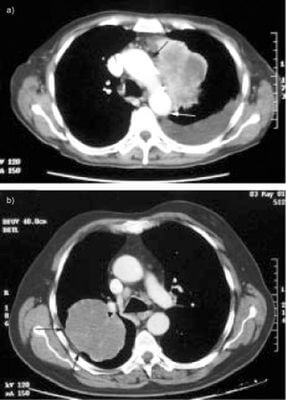

КТ часто використовується для виявлення раку на ранніх стадіях або для підтвердження підозри на діагноз. КТ може виявити наявність пухлин, їх розмір і розташування, а також те, чи поширилися вони на інші частини тіла. КТ особливо корисна для виявлення солідних пухлин, таких як рак легенів, печінки та підшлункової залози.

Після того, як рак діагностовано, КТ використовується для визначення масштабу захворювання та стадії раку. КТ може виявити, чи поширився рак на лімфатичні вузли або інші органи, що допомагає прийняти рішення про лікування.